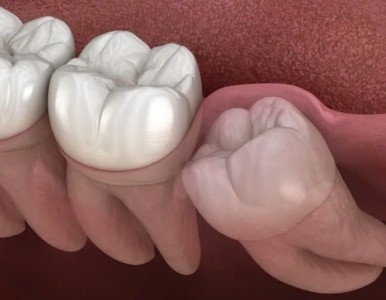

Răng khôn (răng số 8) thường mọc lệch, mọc kẹt gây đau, viêm nhiễm và nhiều biến chứng nguy hiểm. Cùng Nha Khoa SV tìm hiểu khi nào nên nhổ răng khôn an toàn.

Tìm hiểu dấu hiệu răng khôn mọc lệch, mức độ nguy hiểm và cách xử lý an toàn. Bài viết cung cấp thông tin đầy đủ, kèm video thực tế tại Nha Khoa SV.

Tìm hiểu răng số 8 (răng khôn), dấu hiệu mọc, các dạng nguy hiểm và phương pháp nhổ răng khôn chuẩn y khoa tại Nha Khoa SV.